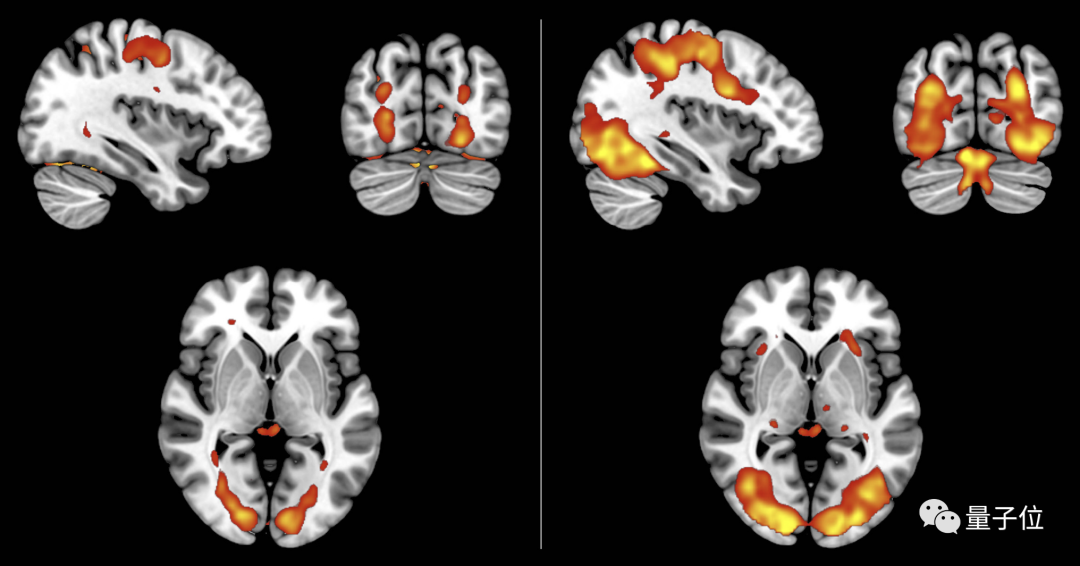

同步进行的大脑活动监测也证实了这一观点。

在想象和真的看到物体时时,前脑岛、辅助运动前区和右侧前额叶皮质三个区域中的活跃部分是重叠的。

解码分析结果也显示,想象与视觉的编码方式是相同的。

大脑活跃区域都一样了,还能不是一回事吗?

尽管原理相同,但大脑在进行两种活动时,神经的活跃程度是不同的。

在真实视觉当中,相关脑区比想象时表现得更为活跃。

统计结果表明,相关神经活跃程度存在某一阈值,超过这一阈值的信号会就会被大脑认作真实视觉。